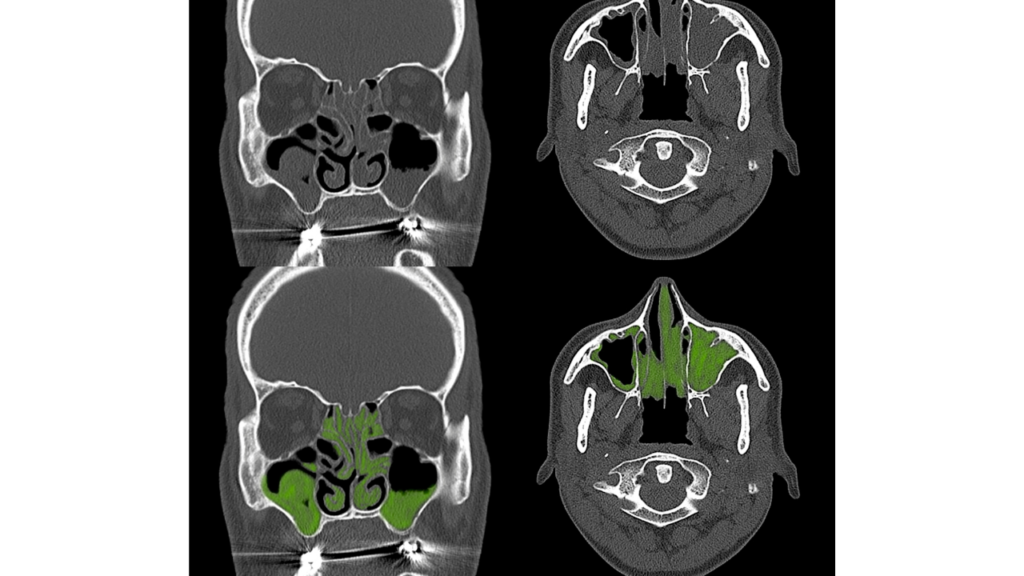

副鼻腔炎とは、鼻の奥にある「副鼻腔」に炎症が起こる疾患です。

この副鼻腔に膿がたまり続ける状態を「蓄膿症」と呼びます。